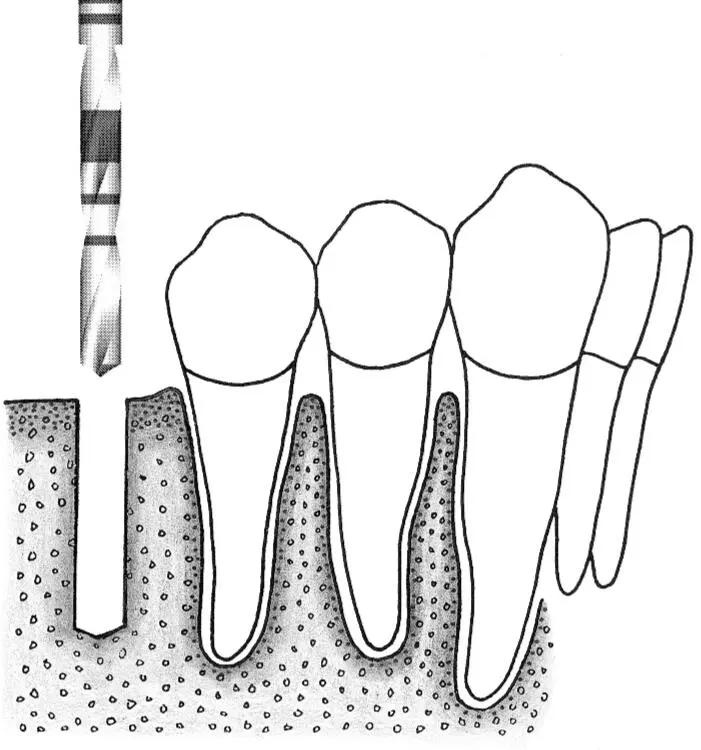

Fig 1-2Sequence of site preparation for a standard implant.

Fig 1-2a A no. 1 round bur is used to mark the position of the implant site.

Fig 1-2b Access is widened with a no. 2 round bur. This step makes it possible to correctly position the next drill.

Fig 1-2c The initial implant site preparation is made with a 2.2-mm-diameter pilot drill.

Fig 1-2d A 2.2-mm-diameter guide pin is inserted into the initial preparation to check its position and axis.

Fig 1-2e The crest of the osteotomy is enlarged with a no. 3 round bur.

Fig 1-2f A 2.8-mm-diameter spiral drill is easily inserted for preparing the depth of the site.

Fig 1-2g A profile drill is used to further increase the surgical access for the next, larger-size drill.

Fig 1-2h Preparation of the implant site continues with the 3.5-mm-diameter spiral drill.

Fig 1-2i Occasionally, when the bone structure is uniformly dense, bone tapping is performed prior to implant placement.

Fig 1-2j A standard implant is placed in the site, with the rough surface positioned at the level of the alveolar ridge crest. This allows the implant shoulder to be located at the gingival level.